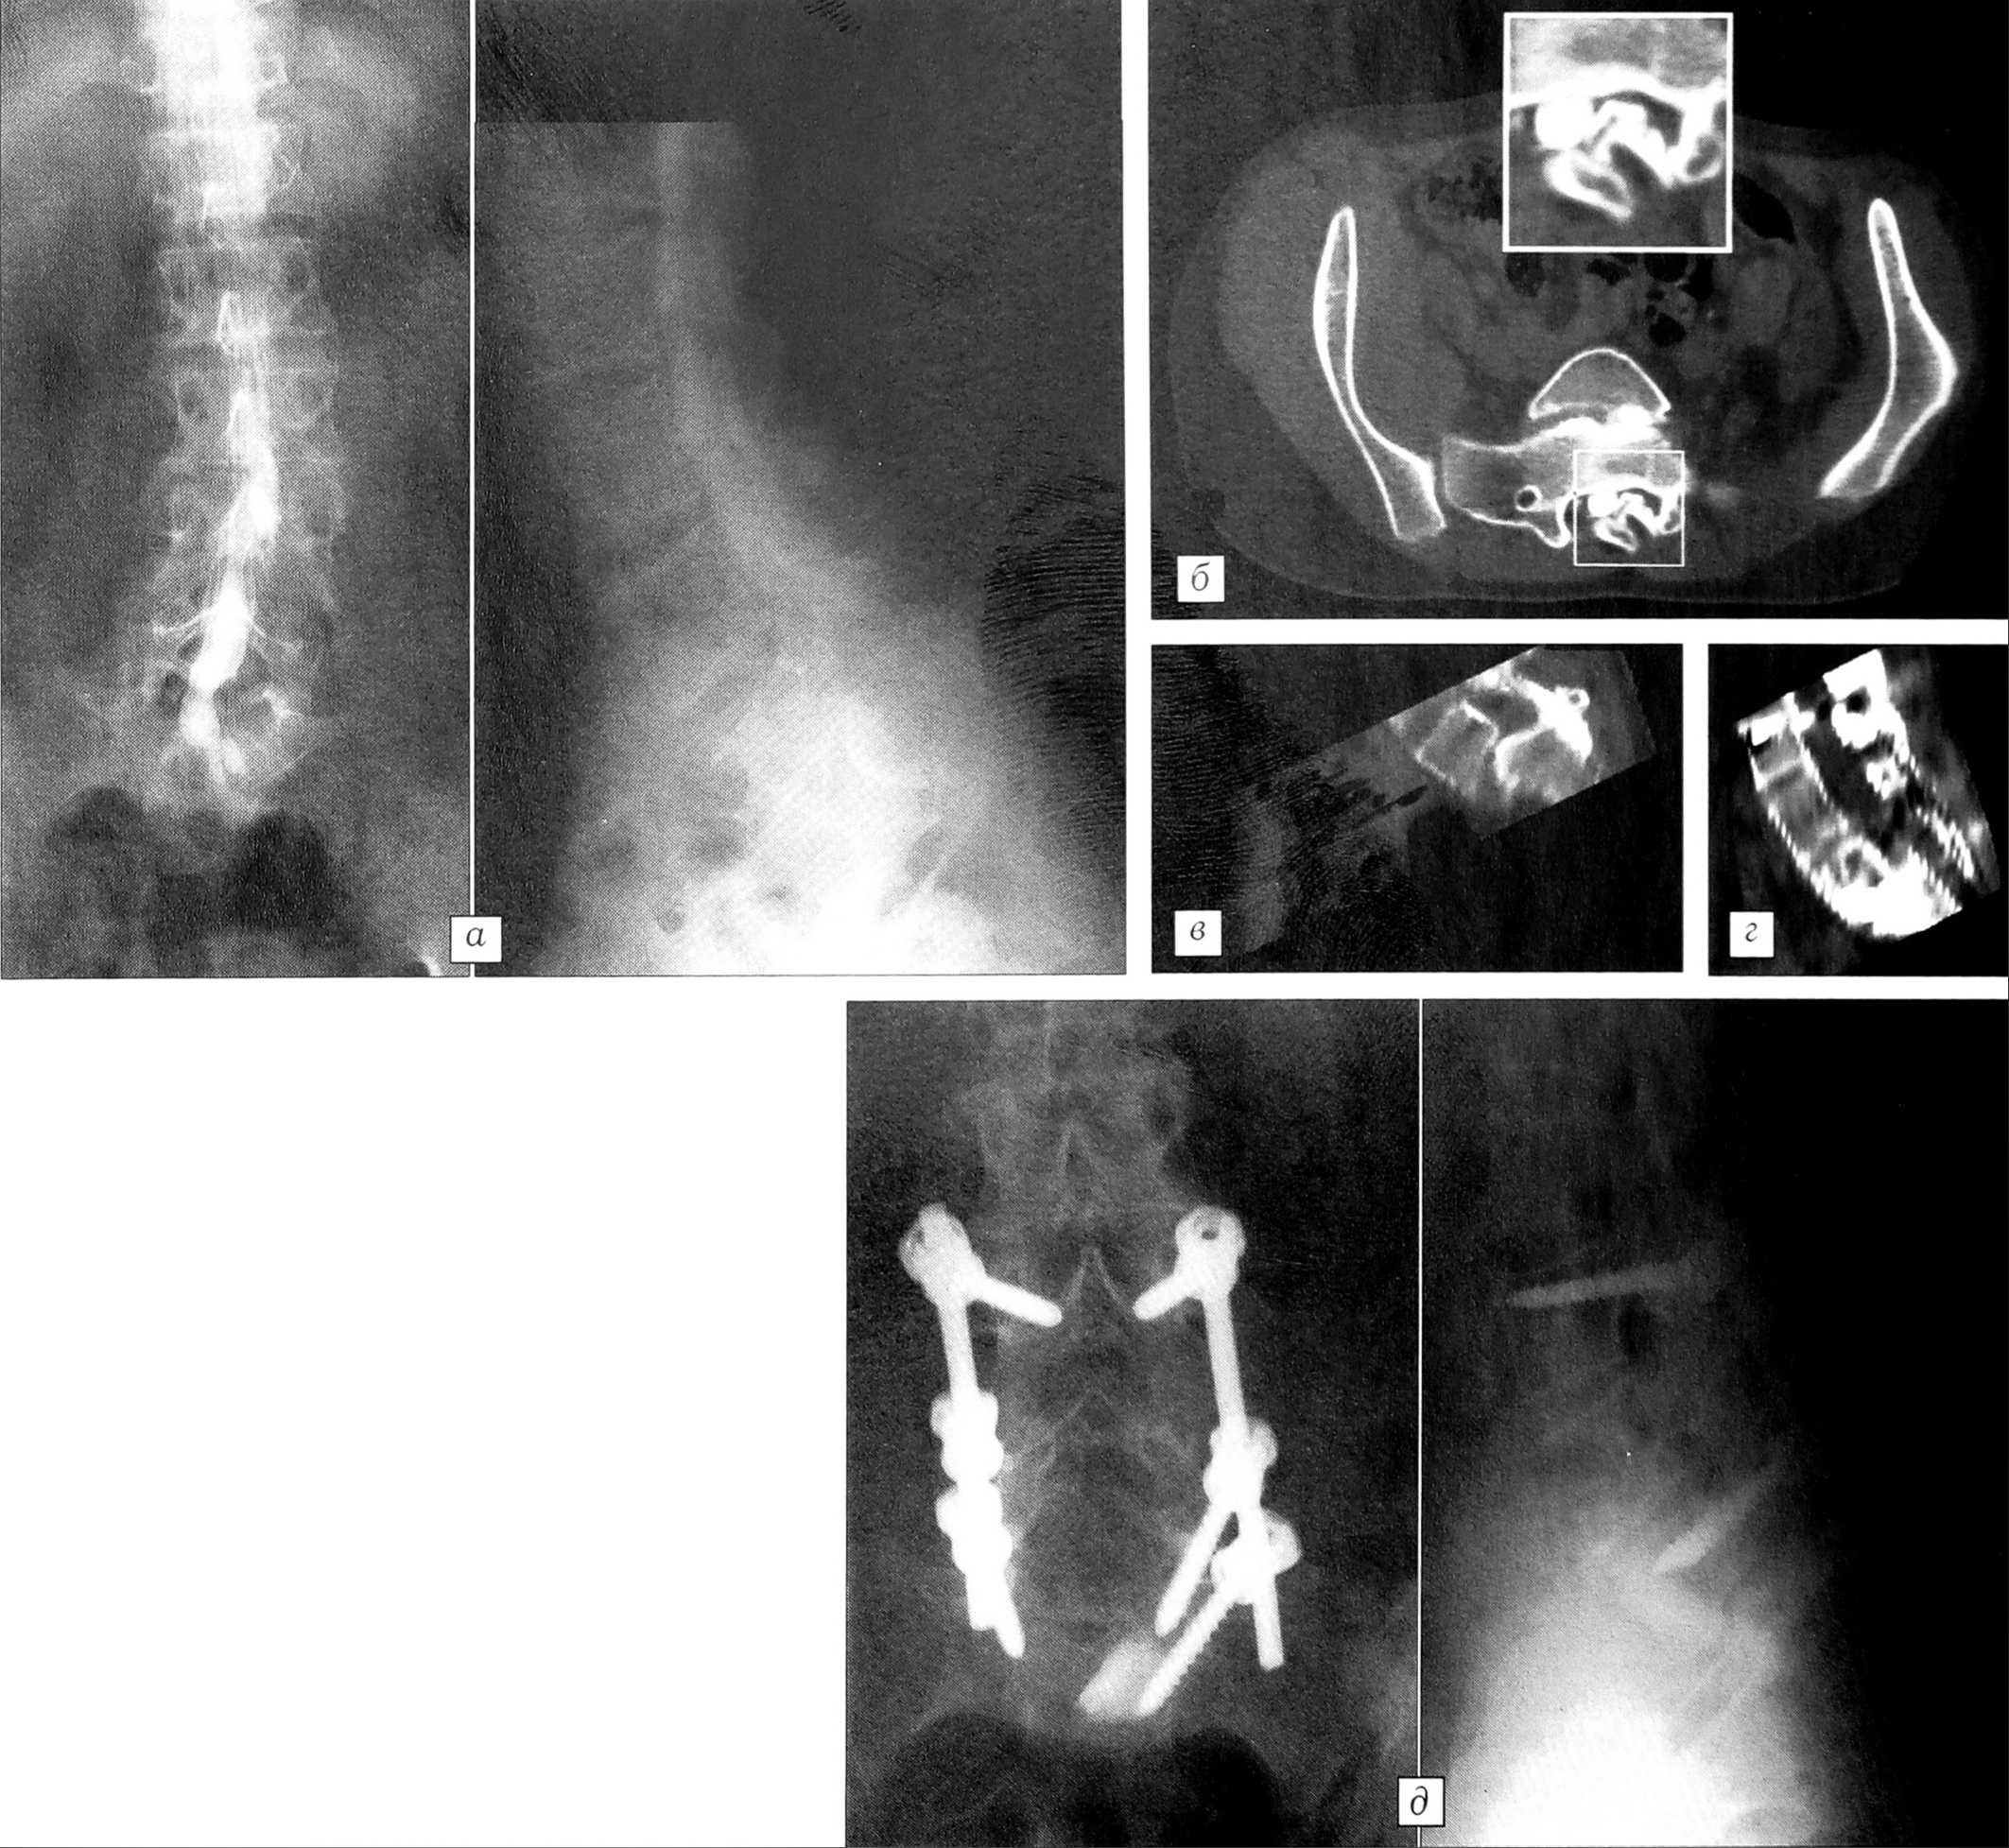

Рис. 2. Рентгенограммы больного А. 8 лет. Диагноз: спондилолизный спондилолистез L5 позвонка III степени.a — до операции;б — после операции: редукция до II степени;в — через 8 лет после операции: редукция смещения практически до I степени.

При применении дистракторов Казьмина не удавалось достичь значительного вправления смещенного позвонка. Исключение составил один больной — мальчик 8 лет со спондилолизным спондилолистезом L5 позвонка III степени, у которого после установки дистракторов в процессе роста произошла редукция смещения до I степени (рис. 2). Дистракция пояснично-крестцового отдела позвоночника за счет рассматриваемой конструкции приводила к расширению межпозвонковых отверстий и тем самым — к частичной декомпрессии нервных корешков в месте выхода из позвоночного канала, что способствовало устранению болевого синдрома. Положительной стороной являлось также уменьшение при установке дистракторов исходного гиперлордоза (особенно у больных с IIIIV степенью смещения) практически до физиологической величины. Это благоприятно сказывалось как на косметическом эффекте операции, так и на восстановлении биомеханических взаимоотношений в пояснично-крестцовом отделе.

Применение транспедикулярных конструкций давало нам возможность добиваться адекватной редукции смещенного позвонка. Степень редукции планировали в соответствии с функциональными рентгенограммами. Так, у детей и подростков смещение позвонка на функциональных снимках уменьшалось на I—II степени — соответствующая редукция достигалась на операции. Представляет интерес уже упомянутый выше случай, когда у мальчика 8 лет со спондилолизным спондилолистезом L5 позвонка III степени после двухэтапного оперативного лечения (фиксация дистракторами Казьмина и передний спондилодез аллотрансплантатом) первоначально была достигнута незначительная редукция, а в процессе роста ребенка произошло самовправление смещенного позвонка до I степени (см. рис. 2). У пациентов средней и старшей возрастных групп мобильность позвоночника на уровне смещения была значительно меньше, а при дегенеративном спондилолистезе возможность вправления фактически отсутствовала изза выраженных явлений спондилеза и спондилоартроза. В таких случаях мы не предпринимали попыток вправления позвонка, а ставили целью прежде всего обеспечить стабильную фиксацию на существующем уровне.